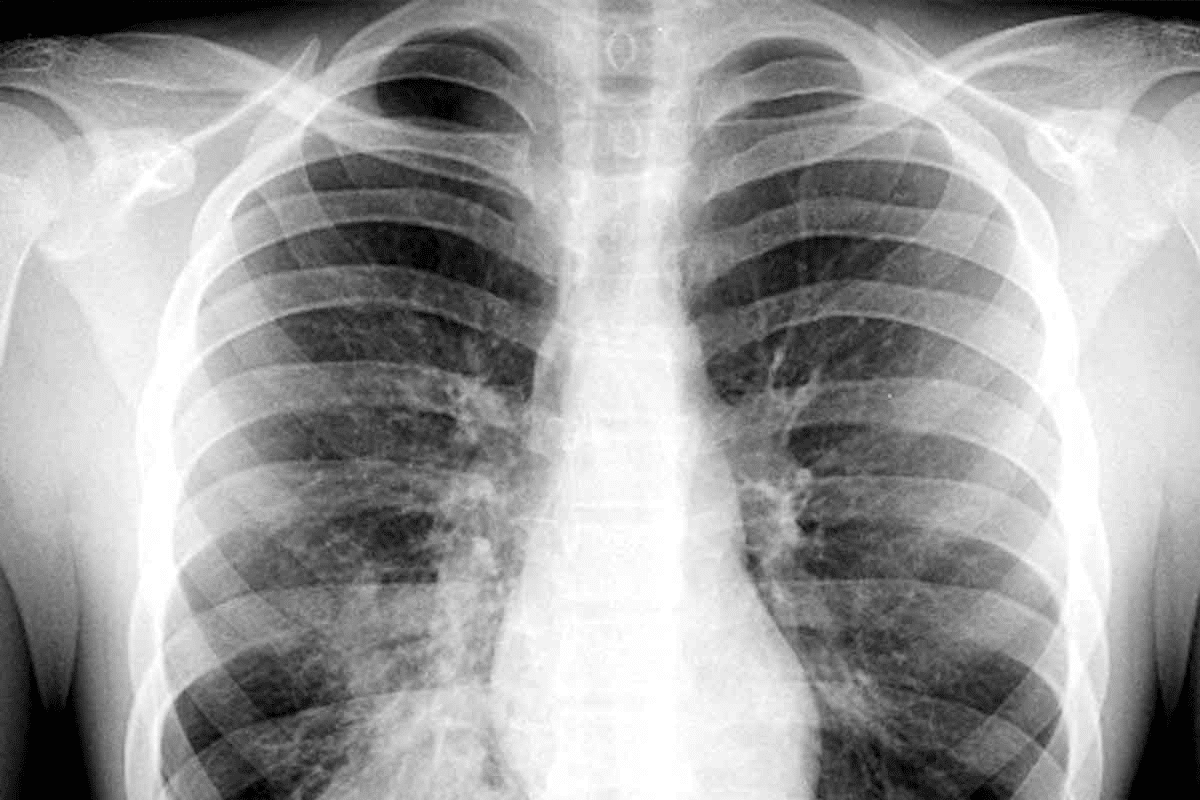

Imaging Studies

Imaging, like chest X-rays, is vital for diagnosing pneumonia. X-rays show how much of the lung is affected and any complications.

At times, CT scans are needed for more detailed lung evaluation or to spot complications not seen on X-rays.

Chest X-ray |

Assess lung involvement |

Infiltrates or consolidation |

By combining clinical evaluation, lab tests, and imaging, we can accurately diagnose viral pneumonia. This helps us create a treatment plan that meets the patient’s needs.